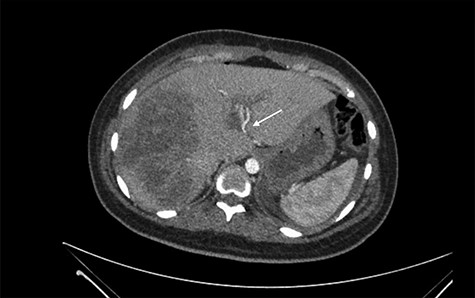

She was referred to our center on postoperative Day 4 due to progressive jaundice and encephalopathy. A triphasic contrast-enhanced abdominal computed tomography (CT) was done revealing a right liver lobe infarct, absence of the right and left hepatic arteries (Fig. 1), presence of an accessory left hepatic artery from the left gastric artery (Fig. 2) and right portal vein thrombosis with extension to the main portal vein (Fig. 3).

Accessory left hepatic artery (white arrow) on the arterial phase of the triphasic contrast-enhanced abdominal CT.